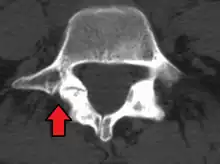

CT scan

Computed tomography can be helpful in evaluating bony vertebral abnormalities, such as fractures.[29] This can be helpful in determining if the fracture is a new, old, or progressing fracture.[29] CT use in spondylolisthesis evaluation is controversial due to high radiation exposure.[30]

Isthmic anterolisthesis is where there is a defect in the pars interarticularis.[34] It is the most common form of spondylolisthesis; also called spondylolytic spondylolisthesis, it occurs with a reported prevalence of 5–7 percent in the US population. A slip or fracture of the intravertebral joint is usually acquired between the ages of 6 and 16 years, but remains unnoticed until adulthood. Roughly 90 percent of these isthmic slips are low-grade (less than 50 percent slip) and 10 percent are high-grade (greater than 50 percent slip).[31] It is divided into three subtypes:[35]

• A: pars fatigue fracture

• B: pars elongation due to multiple healed stress effects

• C: pars acute fracture